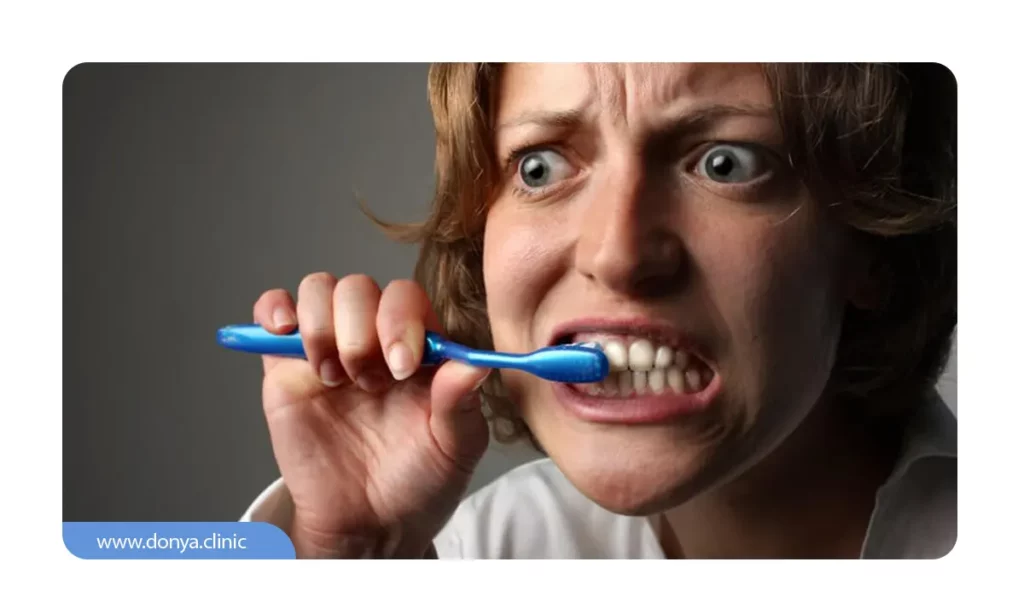

3. مسواک زدن تهاجمی

بیش از حد مسواک زدن، وارد کردن فشار زیاد به دندان ها حین تمیز کردنشان، استفاده از مسواک های نامرغوب و موارد مشابه باعث تحلیل دندان و عقب نشینی شوند. مسواک باید نرم باشد و بدون هیچ فشاری مسواک زده شود.